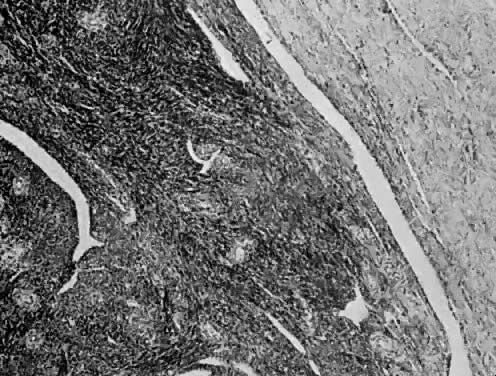

Endolymphatic Stromal Myosis

Numerous authors have reported that endometrial stromal myosis occurs predominately in premenopausal women.39,40,41 Bard and Zuna reported an average age of 42 years.40 Endolymphatic stromal myosis is composed of nodules of stromal cells with rounded nuclei and dense cytoplasm (Fig. 6). These tumors have frequently been confused with endometrial stromal sarcoma. The determination of the number of mitotic figures per 10 HPF is important in separating these two tumors. Endolymphatic stromal myoses have fewer than five mitotic figures per 10 HPF, and they have pushing rather than infiltrating margins (Fig. 7). Although these tumors have an innocuous appearance and prolonged clinical course, they can be fatal. The 5-year survival reportedly ranges from 66% to 100%.19,34,40 Some of these tumors reportedly contain estrogen and progesterone receptors.41,42 This may be the reason why some of them are sensitive to progesterone therapy. Bard and Zuna reported that nearly 40% of their Stage 1 endometrial stromal myosis (low grade) eventually recurs in the pelvis, abdominal cavity, and lungs. These recurrences may manifest themselves years after primary therapy.39,43,44

Fig. 6. Cellular detail of endolymphatic stromal myosis. The cells are uniform. There is minimal cellular atypia and no mitosis (H&E, × 350)

Fig. 7. Endolymphatic stromal myosis showing pushing margin (H&E, × 90)